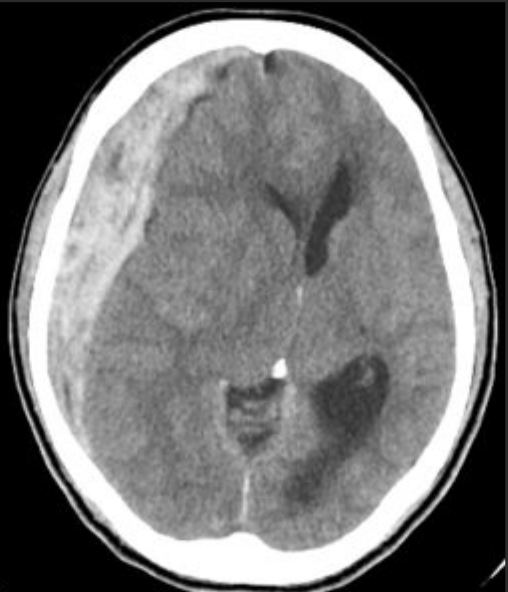

急性硬膜下血腫(Acute Subdural Hematoma)

脳の表面は硬膜という白色の厚い膜に覆われています。頭部外傷により硬膜の血管、架橋静脈や脳表の血管が損傷すると硬膜と脳表の隙間に血液が溜まります。硬膜側(外側)には頭蓋骨があるため、溜まった血液の圧力は、脳側(内側)に逃げるしかなくなります。すると脳は外側より圧迫され、逃げ場がなくなると脳ヘルニアという状態になり生命の危険に陥ります。その場合、緊急開頭手術が不可避となります。非常に予後不良な病態の1つです。

小児と高齢者の重傷頭部外傷においては最多であり、通常、受傷直後から重篤な意識障害を呈しますが、数分から数時間の意識清明期(意識状態がはっきりしている期間)の後、頭痛・嘔吐・意識障害を呈する恐れがあるため、注意が必要です。